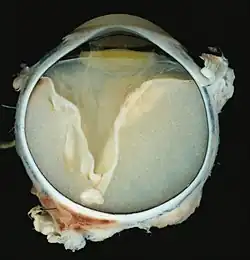

V-förmige Ablösung der Netzhaut durch das Exsudat. -

Vollständige Ablösung der Netzhaut durch das Exsudat.

Eine ausgeprägte Netzhautablösung und ein gelbliches Exsudat unter der Netzhaut, das Cholesterinkristalle enthält, sind charakteristisch für den pathologischen Befund.

Unter dem Mikroskop kann die Wand der Netzhautgefäße in manchen Fällen verdickt, in anderen ausgedünnt erscheinen. Hinzu kommt eine unregelmäßige Erweiterung der betroffenen Gefäße.[25] Charakteristisch ist ein Exsudat, das sowohl aus Cholesterinkristallen, mit Cholesterin und Pigmenten beladenen Makrophagen, als auch aus roten Blutkörperchen und Hämosiderin besteht.[26] An der Netzhaut können sich eine durch das Exsudat ausgelöste granulomatöse Reaktion und in manchen Fällen auch eine durch die Verletzung ausgelöste Gliose finden.[27]